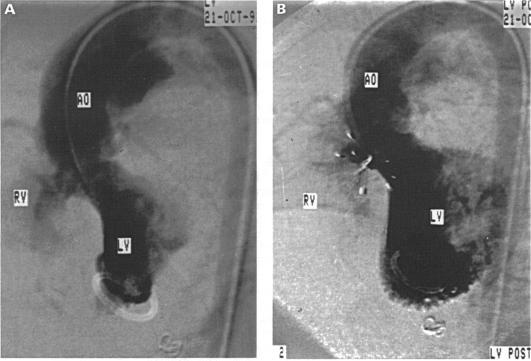

The starting hypothesis was that some perimembranous ventricular septal defects can be closed safely and effectively with a Bard Rashkind double umbrella introduced through a long transvenous sheath.

A modified Rashkind ductal double umbrella was introduced through a long transvenous sheath and positioned on either side of the ventricular septal defect. Placement was guided by transoesophageal echocardiography.

10 out of 13 patients underwent successful partial or complete closure of a perimembranous ventricular septal defect. There were three placement failures. Two of these were associated with a ventricular septal defect too large for the umbrella device. In a third case the umbrella was opened in the left ventricular outflow tract necessitating surgical removal and closure of the ventricular septal defect.